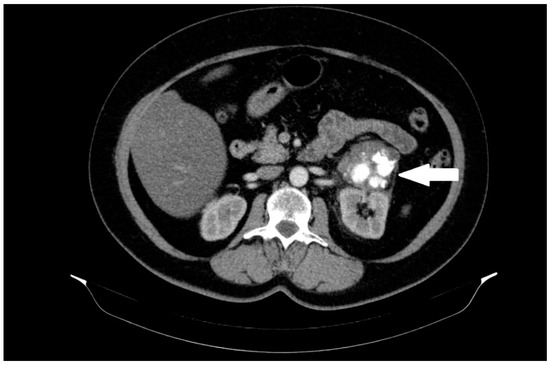

A 60-year-old female patient was admitted to the hospital in December 2022 for surgical treatment of a tumor in the left renal region. The patient reported periodic abdominal pain, general weakness, and no other complaints for about half a year. A follow-up abdominal ultrasound (USG) revealed a tumor in the left renal region. Computed tomography (CT) of the abdomen, pelvis, and chest was added to the diagnostic work-up. A CT scan revealed a 56 mm heterogeneous mass in the region of the left renal hilum with an equivocal exit point (Figure 1).

Figure 1.

A heterogeneous solid mass, 56 mm in diameter, located between the left kidney, adrenal gland, and pancreas, with massive calcifications and an unclear exit point. The lesion is marked with an arrow.